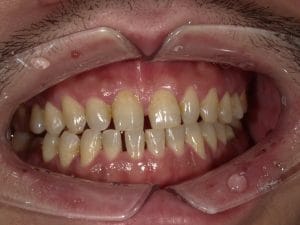

Case032

メジャーリーグでも活躍した元プロ野球選手の山口俊さんのセラミック治療を担当いたしました。

「他院で治療を受けたセラミックが欠けた」というのが主訴でしたが、よく診察するとセラミック欠けただけではなく、被せ物がしっかりと合っていないことが原因で歯茎の腫れがあり、歯石や汚れもつきやすい状態でした。また、歯列も若干歪んでいたので、この機会に全て治療いたしました。

治療後は透明感のある白さで、綺麗な歯並びになりました。また、セラミックをきちんと綺麗に削って適合よくセットしたことにより、歯茎の腫れも改善しました。

セラミックを入れた所の歯茎が腫れていて悩まれてる方はぜひご相談ください。

綺麗に削って適合よくセラミックをしてあげれば必ず改善します。